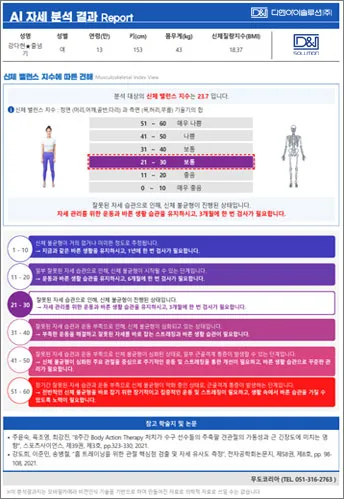

신체 부위별 불균형, 현재 체형의 불균형을 방치했을 경우 예상되는 미래 체형 정보, 신체밸 런스 지 수까지 분석리포트 제공

분석항목 : 거북목, 얼굴비대칭, 어깨불균형, 골반전·후방경사, 신체균형점, 내반슬(O다리), 외반슬(X다리), 반장슬(백니) 등

효과적인 체형 교정을 위한 AI 알고리즘의 신체 불균형 분석